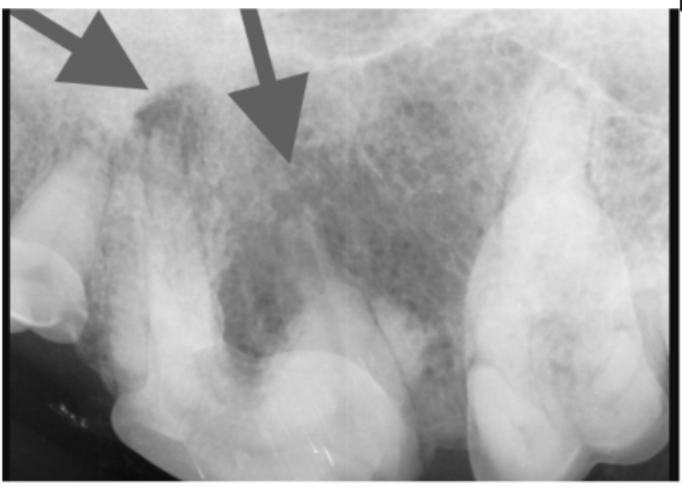

This tooth appeared fine during the oral exam.

The X-ray shows abscesses and tooth resorption, which are painful conditions. The post-operative X-ray shows complete removal of the diseased tooth. The patient healed quickly and felt much better after surgery.